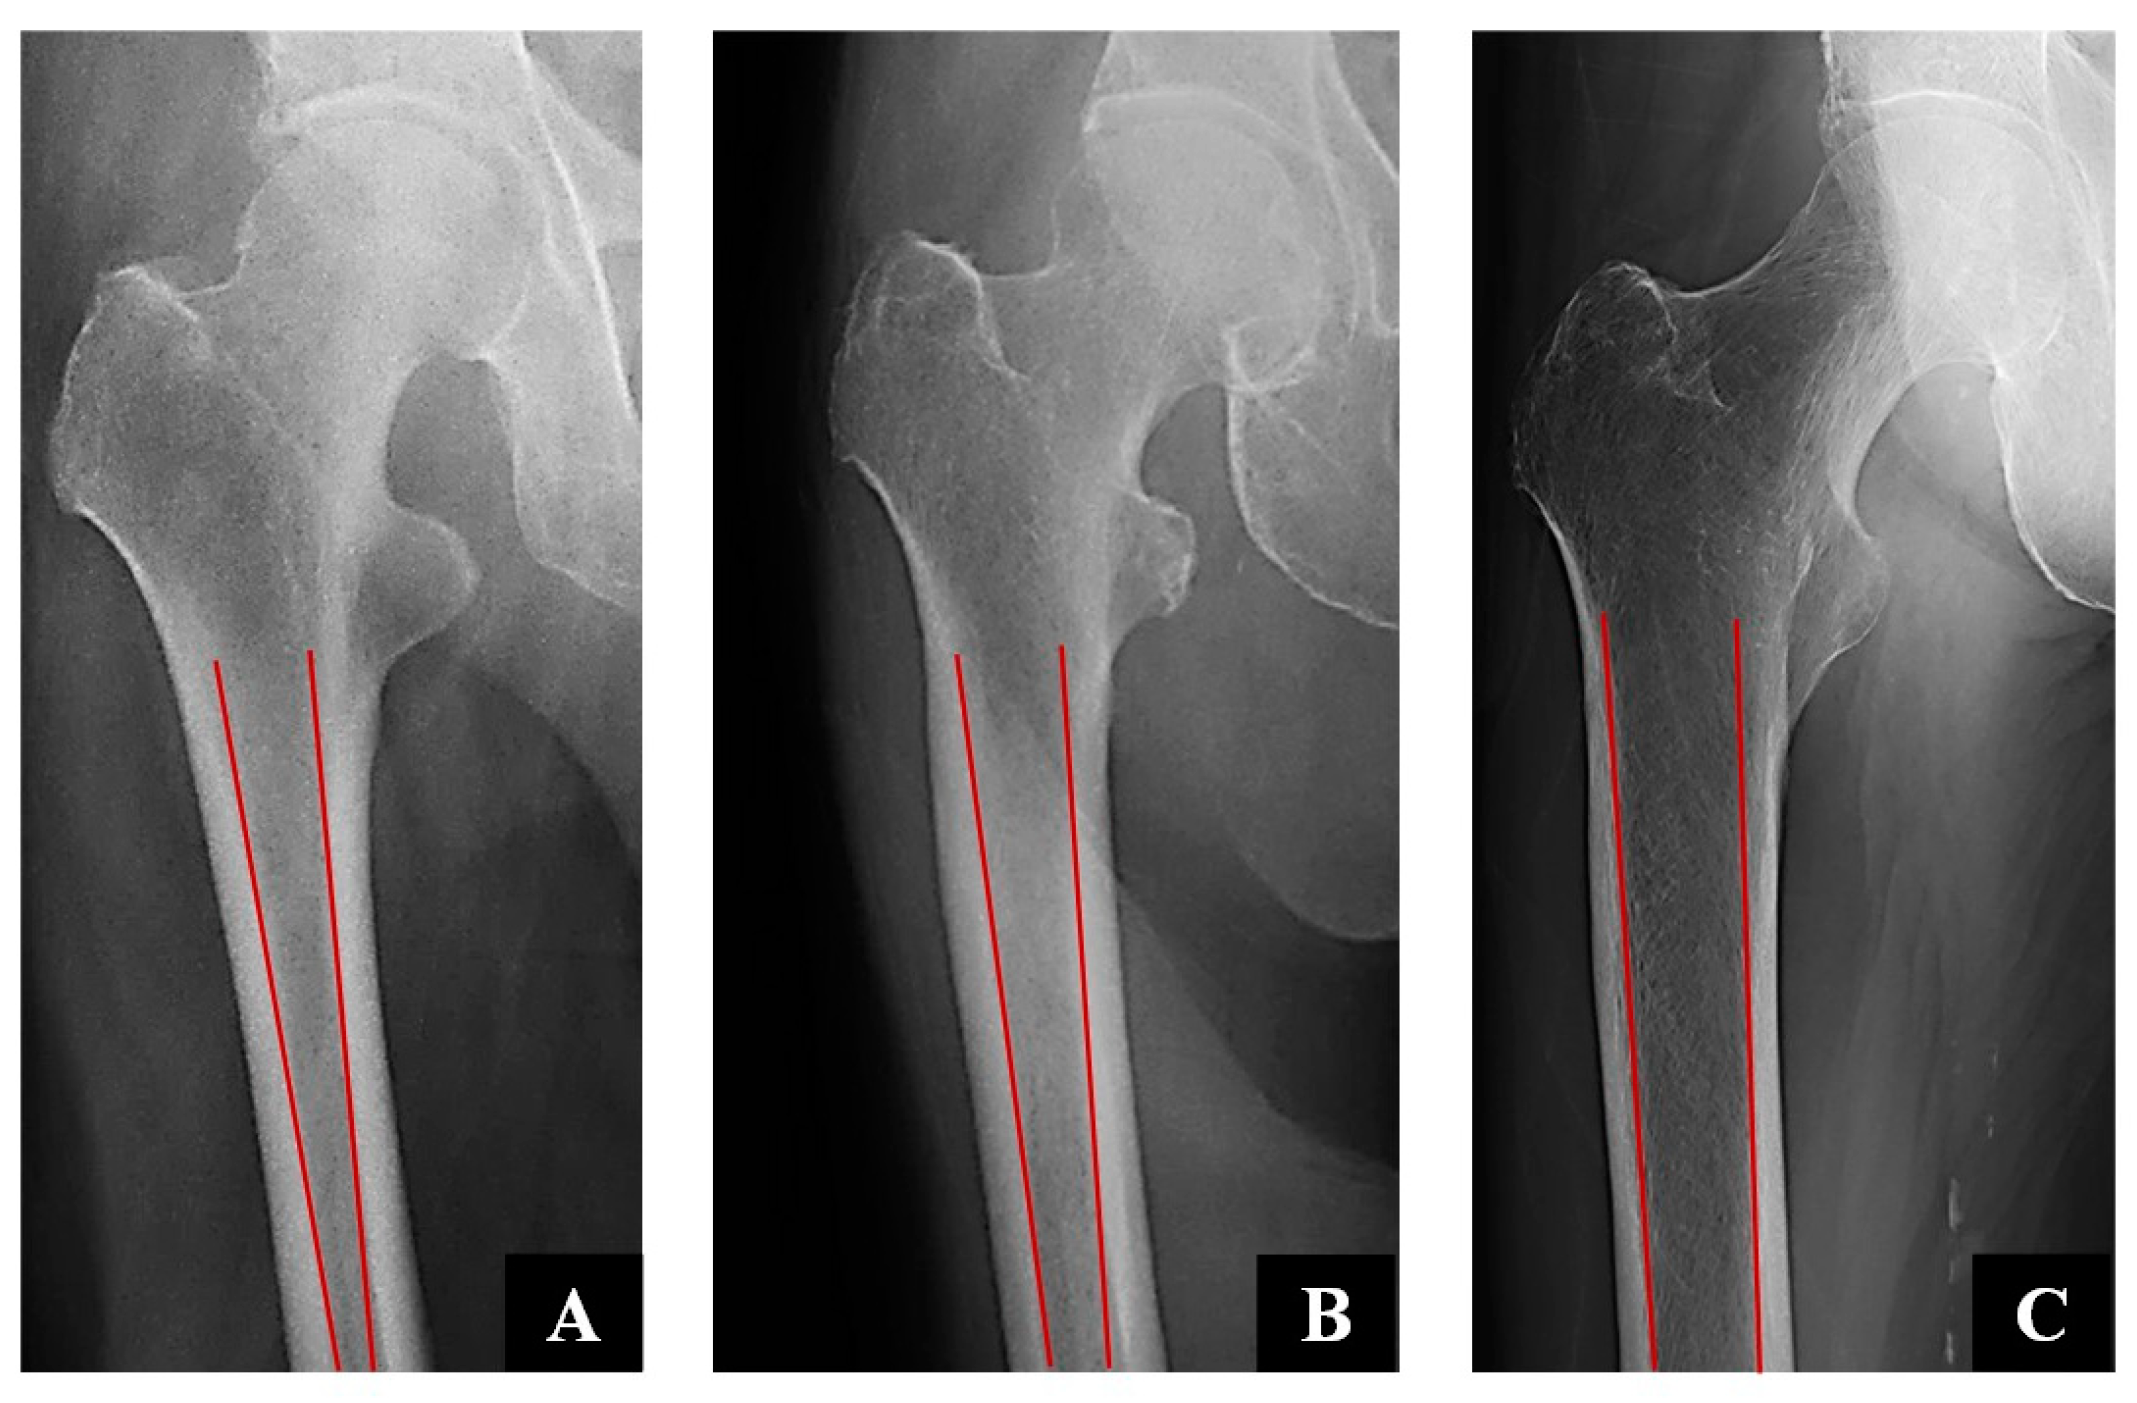

- Dorr, L.D.; Faugere, M.-C.; Mackel, A.M.; Gruen, T.A.; Bognar, B.; Malluche, H.H. Structural and cellular assessment of bone quality of proximal femur. Bone 1993, 14, 231–242. [Google Scholar] [CrossRef]